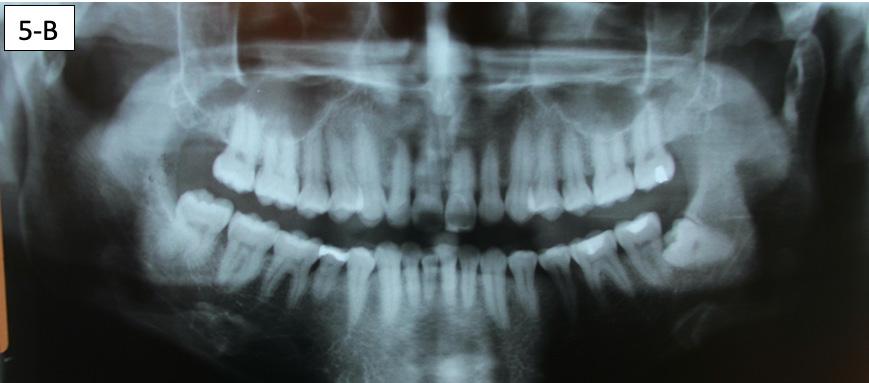

Panoramic radiogram revealed complete permanent dentition with mandibular left impacted wisdom tooth. Roots of the mandibular second bicuspids appeared to be short. There was an excellent bone support and no sign of periodontal or periapical pathology. (Figure 5-B).

FIG. 5A: Pre-treatment, TMJ radiogram

FIG. 5B: Pre-treatment, Panoramic radiogram

FIG. 5C: Pre-treatment, Cephalometric radiogram

FIG. 5D: Pre-treatment,Cephalometric tracing